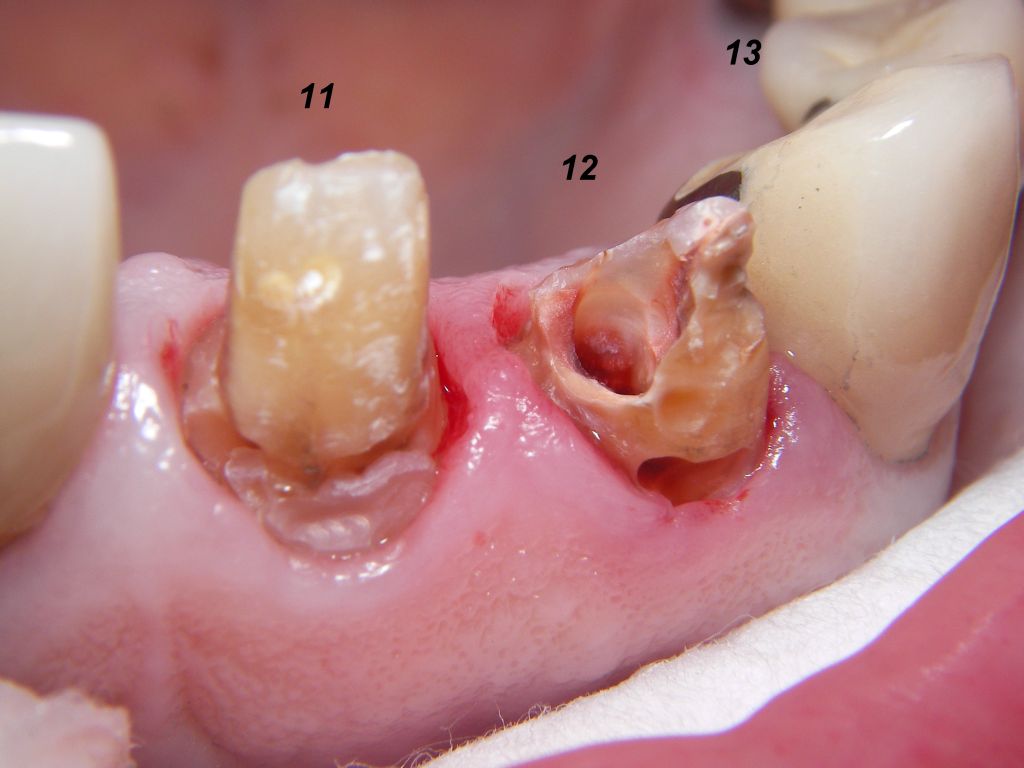

Weil auch die anderen Schneidezahnkronen (12-22) durch Randreparaturen und den schlechten Randschluß erneuerungsbedürftig aussahen, wurden 4 Einzelkronen geplant. Vorher hieß es aber noch, die schlechte Wurzelfüllung im Zahn 12 (Röntgenbild links) besser zu machen. Hierfür wurden am 17.2.06 die alten Kronen 11 und 12 entfernt. Rechts das Bild nach Entfernung von alten Füllungen und Karies. | |

Links nach Wurzelfüllung beim Einpassen des Titanstiftes. Rechts dann der schon provisorisch beschliffene Amalgamaufbau im Zahn 12. |